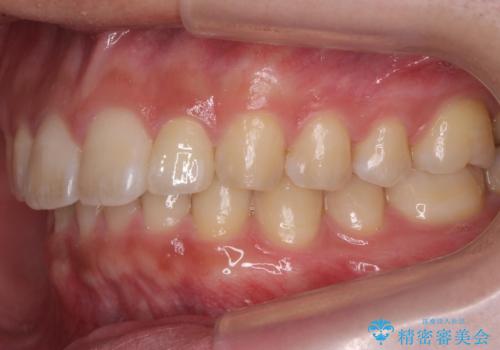

前歯のすき間 小さい歯がある 前歯の並びをきれいにしたい

- 前歯のすき間を気にして来院。

前から2番目の歯が小さく厚みがあったため(矮小歯)

矯正治療で1番目の歯を寄せて2番目の歯はセラミックで形をととのえています。